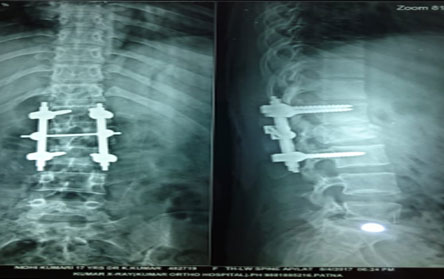

Trauma surgery:

Trauma surgery is a surgical specialty that utilizes both operative and non-operative management to treat traumatic injuries.

The Center of Orthopedics KUMAR ORTHO HOSPITAL ,Patna, offers the entire spectrum of modern orthopedic management, which is effective, patient - friendly & result oriented. In a nutshell, it is one stop treatment for all orthopedic ailments and fractures with emphasis on avoidance of complications, rapid mobilization, decreased period of confinement and an early return to normalcy.